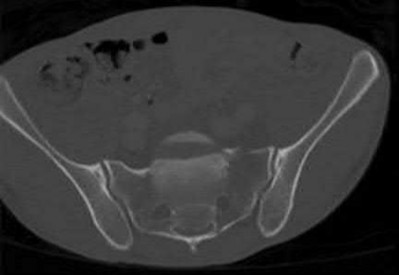

Question 9:

A 24-year-old professional football player sustains a high-energy axial load injury to a plantarflexed foot. Radiographs demonstrate widening of the midfoot spaces. The critical interosseous Lisfranc ligament connects which of the following two osseous structures?

Correct Answer: Medial cuneiform to the base of the second metatarsal

Explanation:

The Lisfranc ligament is a strong interosseous ligament critical for the stability of the tarsometatarsal joint complex. It originates from the lateral aspect of the medial cuneiform and inserts onto the medial aspect of the base of the second metatarsal. There is no direct ligamentous connection between the bases of the first and second metatarsals, making the Lisfranc ligament the primary restraint to lateral displacement of the lesser metatarsals.